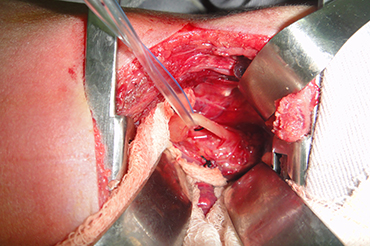

Atresia de Esofago

Neonatal y Lactante